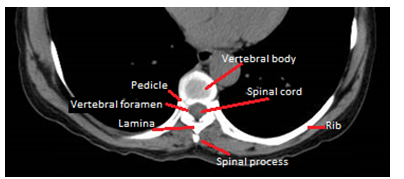

Between the vertebral bodies is the intervertebral disc (Figure 1 & 2), a cartilaginous structure that fulfills the double function of giving primary support to the spine and sufficient elasticity to allow movements of the spine,1 which normally has a biconvex shape.4 This disc is composed of central part by a nucleus pulposus (containing up to 88% of water in young and healthy discs1) that is externally contained by a fibrous annulus.3

Figure 2 Axial view-Parts of thoracic vertebrae.